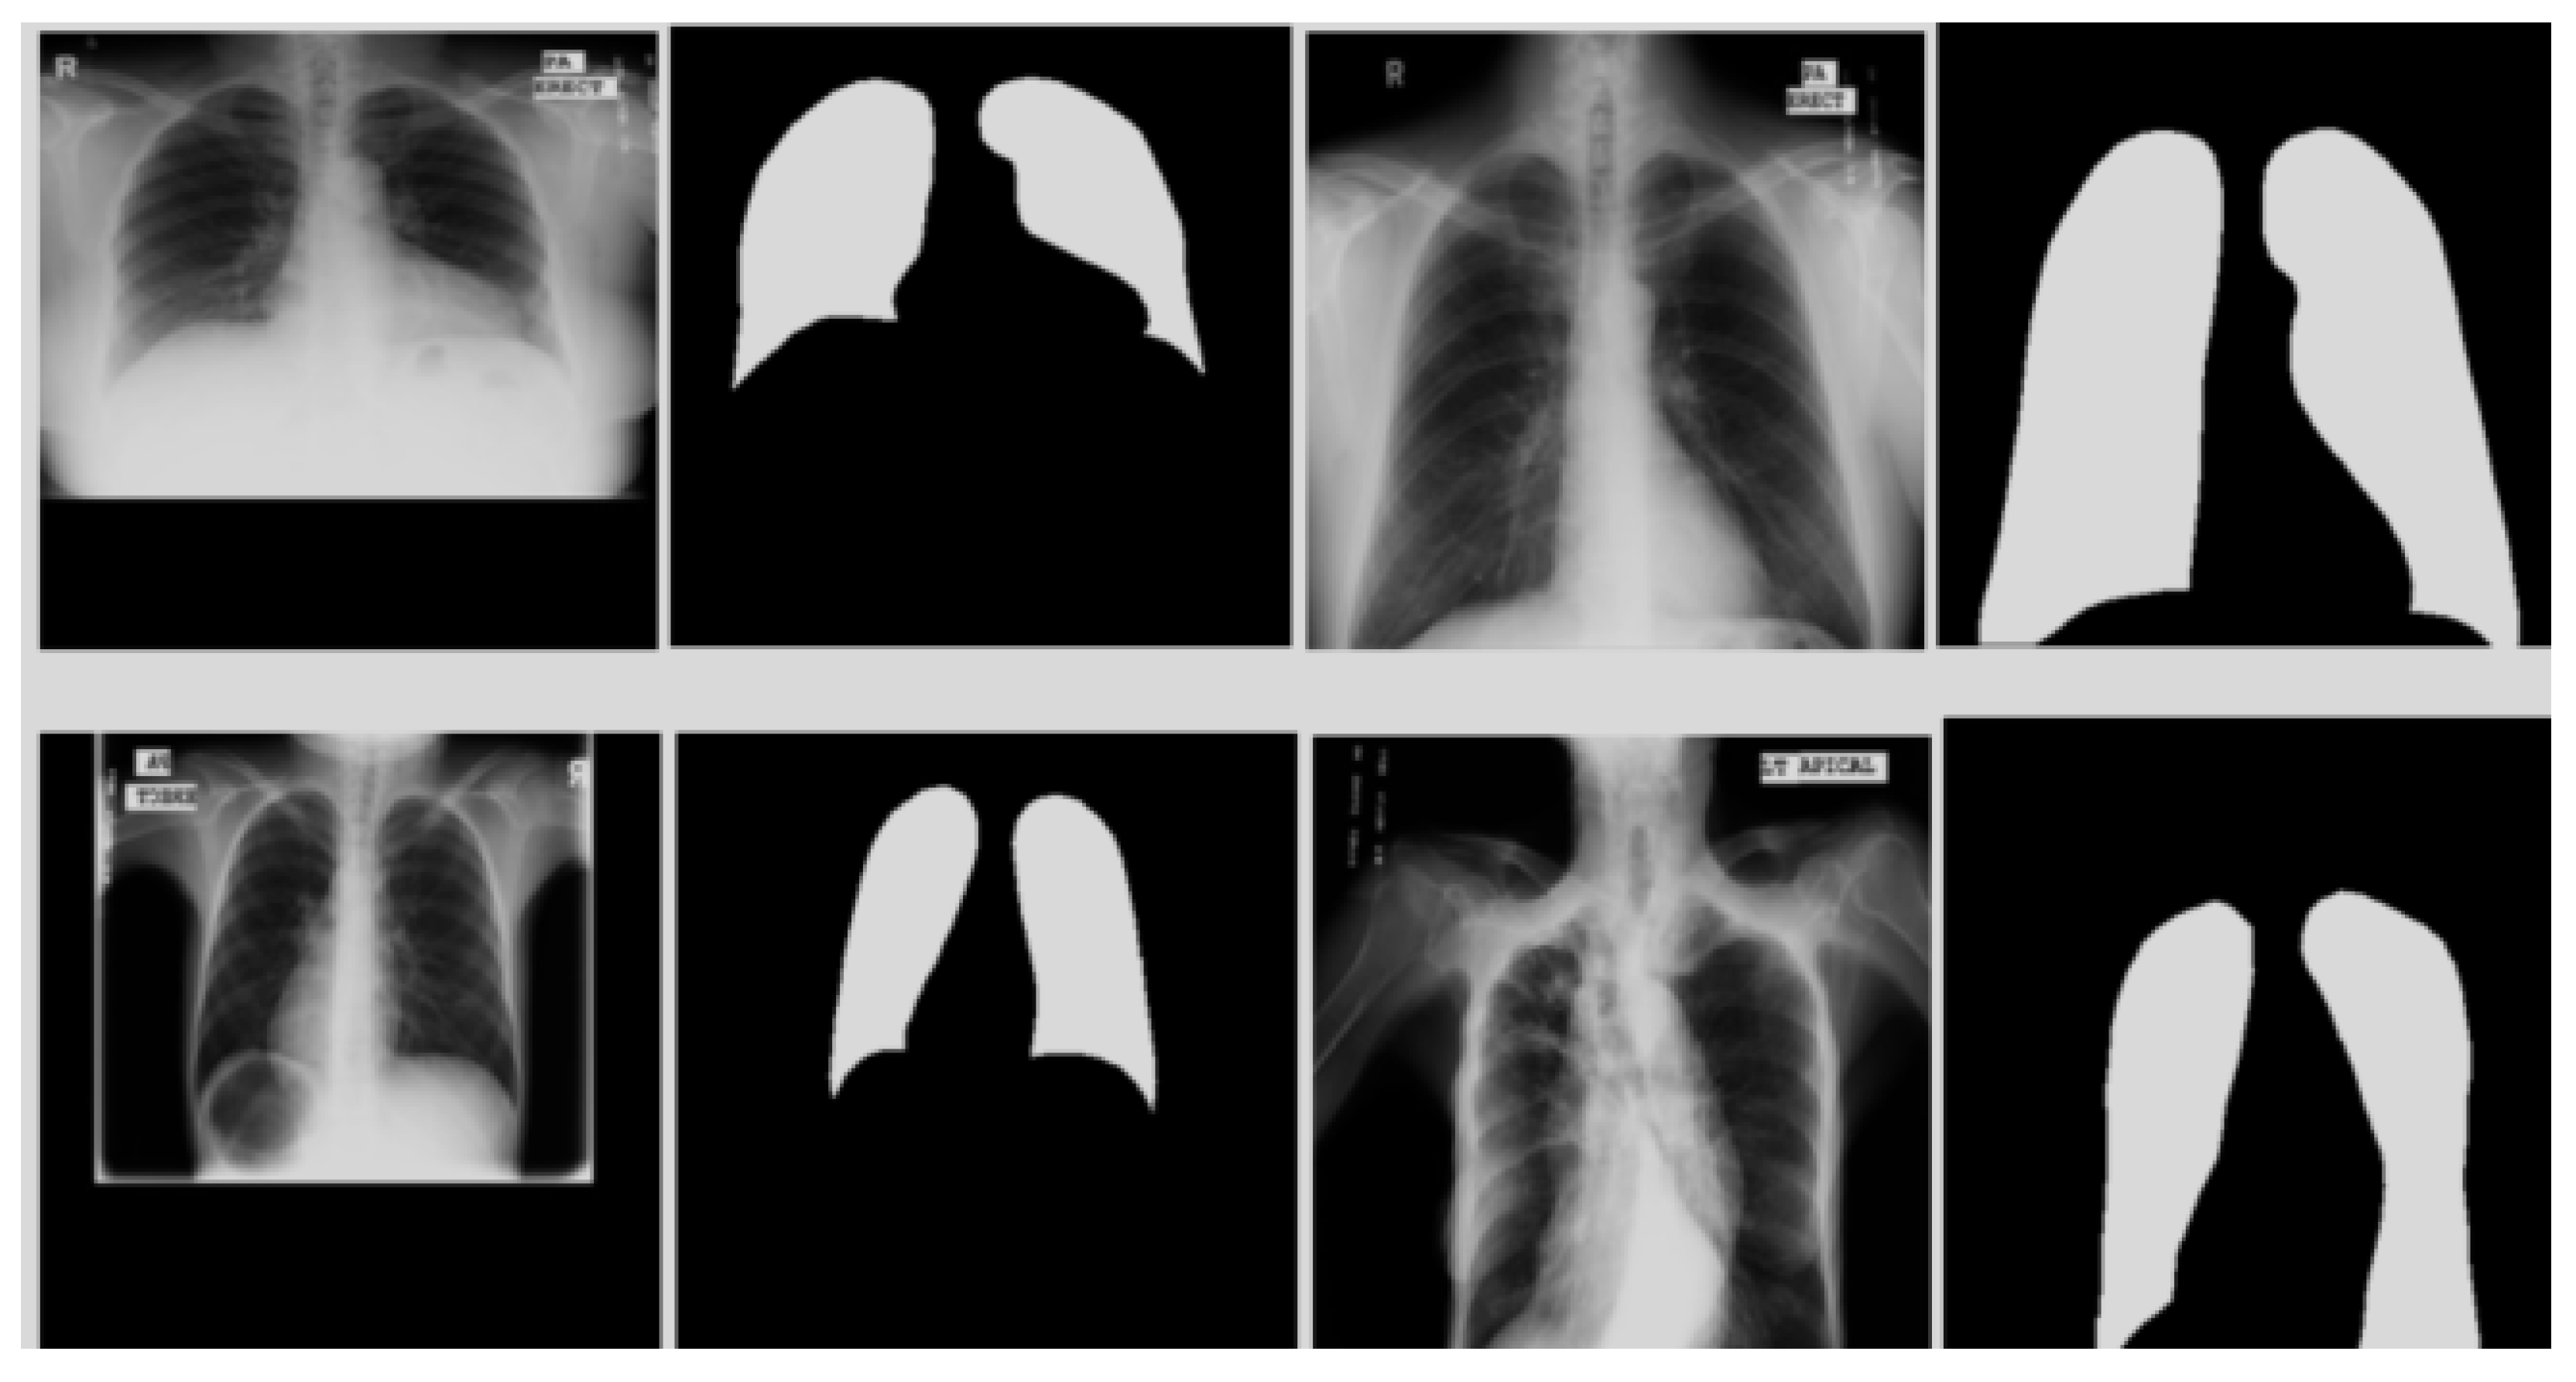

4.3.4. Lung Segmentation from MC Dataset Using CardioNet